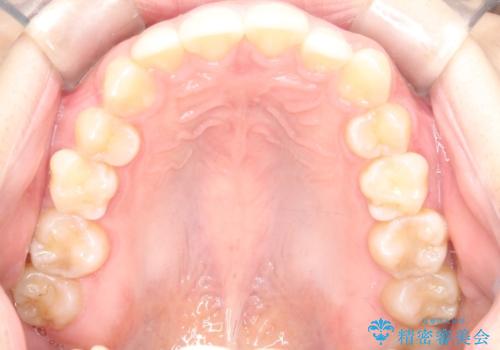

【ワイヤー矯正】前歯のがたがたをなおしたい

- 前歯のがたがたを主訴に来院されました。

叢生量も軽度なため短期間で治療を行っています。

治療中、装置の変更を希望されたため上下で装置が異なっています。